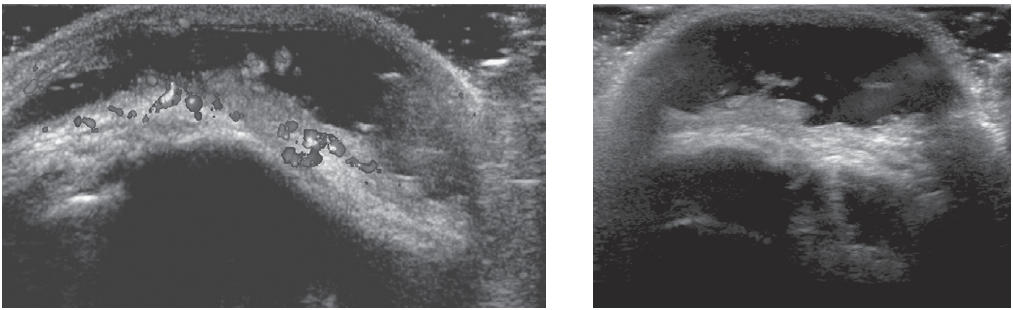

위 사진은 팔꿈치의 주두돌기 위의 세로 방향(우측면이 원위)과 가로방향의 도플러 초음파 영상이다.

초음파 상 점액낭은 연부조직에서 저에코성의 간극으로 보이며, 고에코성의 주변부에 의해 종종 경계지어진다. 이 환자는 단순 외상후 주두점액낭염에서 특징적으로 볼 수 있는 모습이다. 후방음영증가(posterior acoustic enhancement)를 가진 무에코성의 점액낭의 연장이 나타난다. 주두돌기의 피질은 고에코성이며 음영그림자를 동반한다. 오래된 삼출액은 잔해 또는 섬유성 유착이 나타날 수 있다. 점액낭 내의 에코성의 존재는 염증이나 출혈, 감염성 병인을 지시할 수 있다. 출력도플러(Power Doppler)는 종종 염증 환경에서 점액낭성 윤활 경계 내의 증가된 흐름을 종종 보여준다.